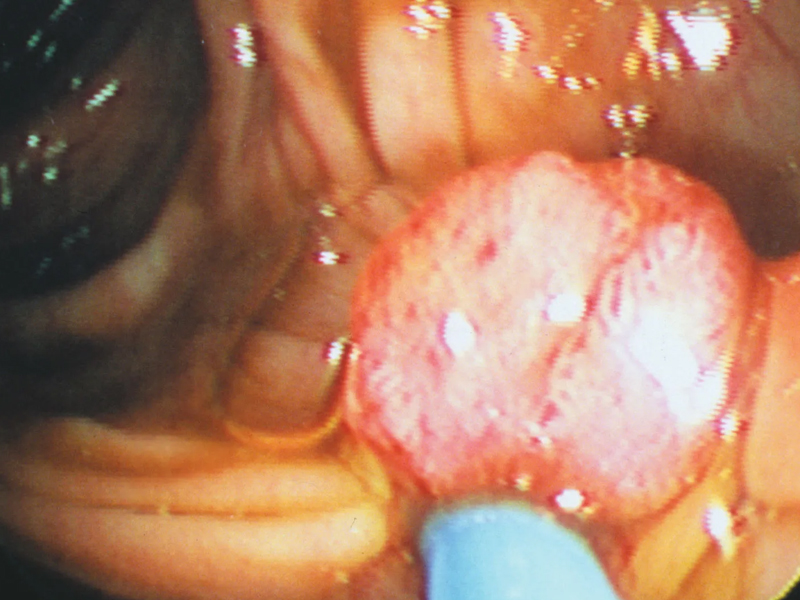

現今上班族多以外食為主,飲食習慣不但油膩且重口味,長期下來容易引發脹氣、便秘等腸道問題。醫生提醒,如果腸胃不適的症狀只出現一兩天,可能只是吃壞肚子,但若有以下 4 大症狀持續 2 周以上,就應該考慮就醫,若持續一個月以上,更應盡早就醫檢查。 醫生分享,腸道是動態的,出現以下4 種情況可能代表腸道出問題了: 食慾不振:如果您突然對食物失去興趣,連自己最愛吃的食物也無法引起食慾,這可能是腸胃問題的前兆。 體重減輕:在未做任何改變的情況下,一個月內莫名其妙地瘦了三公斤以上,這種情況不容忽視,應盡快就醫檢查。 便秘、腹瀉反覆:長達一個月反覆出現便秘和腹瀉,這可能是腸道功能異常的表現。 肚子有硬塊:如果在腹部觸摸到硬塊,特別是偏向一側,這很可能不是簡單的肥胖,應盡快就醫檢查。 一名 30 歲女性患者,四肢纖細但肚子卻異常大,經常被誤以為是懷孕。檢查後發現她肚子有一個凸起的硬塊,且偏右側。如果只是肥胖,腹部不會偏向某一側且應是柔軟的觸感。然而這位患者雖有摸到硬塊,本以為是便秘未太在意,進一步檢查才得知,肚子裡竟有 18 公分大的子宮肌瘤,隨後才轉介給婦產科處理。 腸胃問題不可以輕視,不要只因為症狀出現一兩天就認為是吃壞肚子。應該對自身健康保持警覺,如有以上提到的四種症狀持續 2 周以上,就應該要就醫檢查。腸胃健康不僅影響日常生活,也可能隱藏更嚴重的健康問題,早期發現、早期治療是保護自己健康的最佳方法。 |